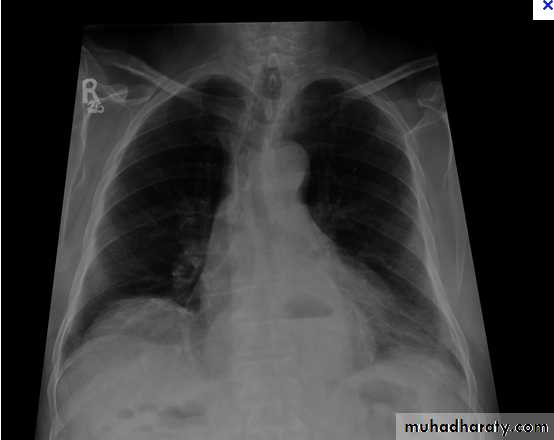

Massive pleural effusion with mediastinal shift to the left.

(A) Chest radiograph

(B) CT coronal reconstruction. A massive effusion displaces the mediastinum to the left. CT shows the important pleural effusion together with the enhanced atelectatic left lung.

Note also the depression of the right hemidiaphragm (arrows).